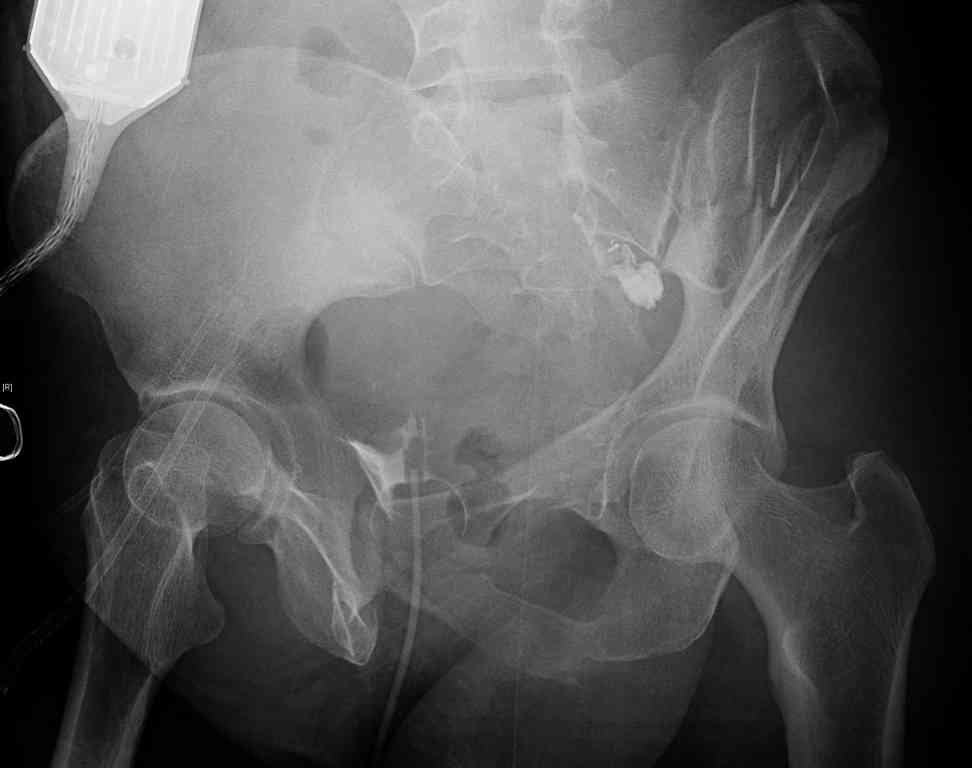

comminuted crescent fx

Ортопедия и травматология Отправлено Jeff Richmond 25 Сентябрь 2007, 22:43

Any advice would be appreciated:

40 ish female ejected from car. Unstable, DPL negative, went to angio and had her pelvic bleeds embolized after many units of blood. GCS 6, floating elbow, clavicle, bothbones, etc.

My standard approach to this pelvis would be posterior, reduce/lag/plate thecrest, reduce/plate the caudal extent on the posterior crest and 1-2 lags back to front. In this case, the crest comminution seems to make plating all the way to the ASIS useless, as the plate would be on free floating fragments. Would plating the posterior extent of the fracture to secure the reduction at the SI joint and 2 screws back to front be sufficient fixation? Would anyone do a perc reduction and perc back to front screws, and would that be sufficient if the SI joint could be reduced (although I don't see how this could be accurately reduced closed). Would an ilioninguinal with a pelvic brim plate and posterior column screws be a better approach, although reducing the SI would be more indirect and less accurate?